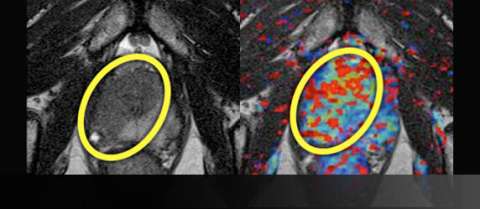

LEFT: T2-weighted image after treatment shows normalization of T2 signal with reappearance of the normal peripheral-transitional zone border.

RIGHT: Color perfusion map shows correspondingly decreased perfusion (blue pixels) consistent with response to treatment.